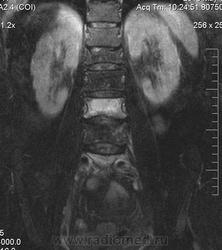

В анамнезе компрессионный перелом тела L1 позвонка в 1981г. На момент обследования компрессионные переломы тел L3, L5 позвонков, думаю остеопоротического характера. Непонятная зона в области боковой массы крестца на уровне S1-S3 слева (объемный процесс?)

Данных за объемный процесс в полости малого таза не вижу, матка удалена давно, шейка матки без особенностей, яичники бы посмотреть, буду рекомендовать УЗИ. Двояковогнутая деформация L3-L5 позвонков наблюдается при остеопорозе. Изменение интенсивности МР-сигнал от тел L3, L5 позвонков думаю, что за счет отека костного мозга в результате не так давно случившихся переломов на фоне остеопороза. Видно, что дуга, нижний суставной отросток L5 позвонка а аналогичными сигнальными характеристиками, вероятно тоже отек.  Непонятная зона в крестце- гемангиома? единичный крупный MTS?(что менее вероятно), изменения остеопоротического характера с возможной трещиной и отеком костного мозга? или еще что-то?

вижу старый перелом L1. ломаются L3,5 позвонки. с характерной для дисгормональной спондилопатии  вогнутостью площадок, отеком костного мозга. На секундарные изменения в крестце,  на мой взгляд, не похоже. А на Т2 как это выглядит?Ярко? Скорее это стрессовые    изменения  от недостаточности.